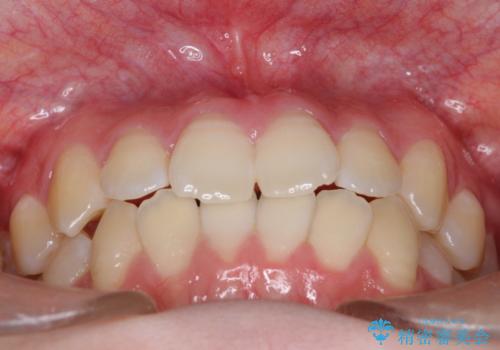

右上小臼歯の捻転を改善|インビザラインと部分ワイヤー矯正のコンビネーション治療

- 右上の小臼歯が大きくねじれており、噛み合わせや見た目に影響を与えている状態でした。診察の結果、インビザライン単独では十分な回転が得られにくいと判断。そのため、基本的な歯列の移動はインビザラインで行いながら、部分的にワイヤー矯正を併用するコンビネーション治療を計画しました。

まず、インビザラインで歯列全体を整えながら、スペースを確保しました。その後、部分ワイヤーを装着し、右上小臼歯の捻転を効率よく改善。ワイヤーの力を活用することで、より確実に歯の向きを整えることができました。治療後は、「しっかり噛めるようになり、見た目も自然になった」と患者様にもご満足いただきました。